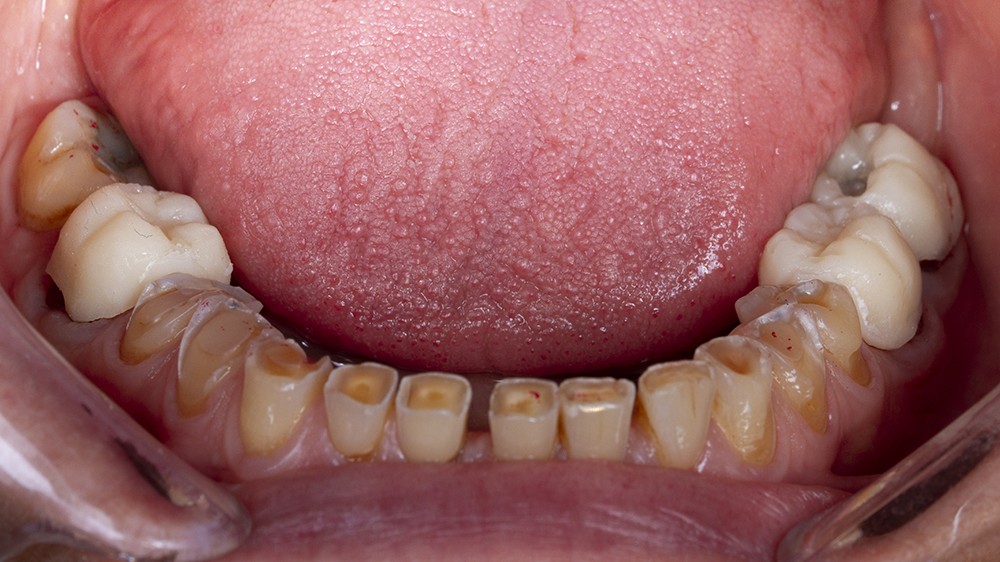

Dans un deuxième temps, un wax-up global permet de restaurer les courbes d’occlusion. Il est à noter que la présence d’égressions dentaires, faute d’antagoniste ou d’anciennes restaurations prothétiques inadaptées, crée des usures inégales au sein de la cavité buccale. Aussi, la présence de zones non recouvertes par le wax-up dans les secteurs postérieurs est courante, permettant ainsi la préservation de zones amélaires majeures pour le collage (fig. 2).